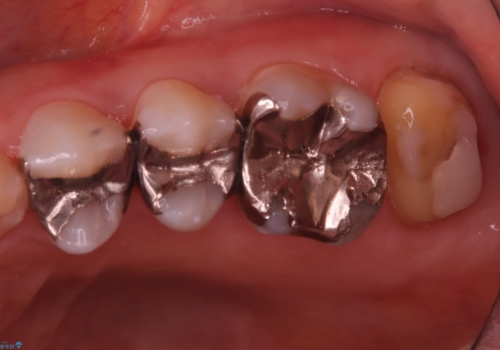

保険適用のメタルインレーと歯質の境目にう窩ができており、補綴物のやり替えとなりなした。

メタルインレーを除去したところう窩が深く、遠心の健歯質が歯肉縁下深くに位置したためディスタルウェッジ術を行い骨と歯肉の高さを下げた上で補綴しています。

元々インレーが入っていましたが、残存歯質量が少なく破折のリスクを説明しジルコニアクラウンでのやり替えとなりました。